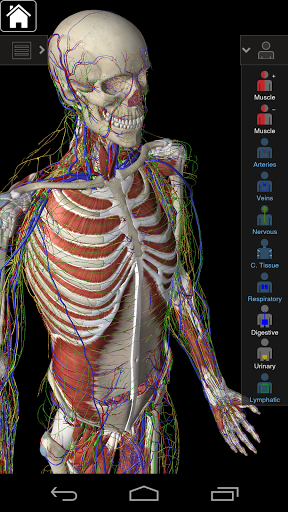

Esta aplicación incluye anatomía esencial para 10 sistemas:

⁃Esquelético

⁃Músculos

⁃Tejido conectivo

⁃Veins

⁃Arteries

⁃Notas

⁃Respiratorio

⁃Digestivo

⁃Urinario

⁃Linfático

⁃también incluye el cerebro y el corazón

La funcionalidad inteligente que se encuentra dentro de la aplicación permite al usuario eliminar capas de músculo a través de la herramienta 'bisturí'. Esta aplicación ofrece a los usuarios la posibilidad de activar / desactivar sistemas sin la necesidad de anular la selección de estructuras individuales o mezclarse en una multitud de pestañas regionales predefinidas, como otras aplicaciones.

---- Modo de selección múltiple - Ocultar / Fundir / Aislar estructuras individuales o múltiples